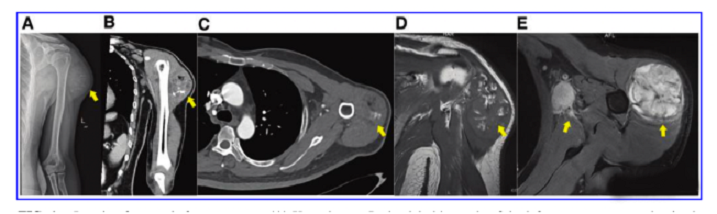

接受iPS細胞治療患者的畸胎瘤。(A) 在左上臂的三角肌中,觀察到一個圓形的混合密度腫塊,邊界不清,為9.6±5.2cm。(B) CT冠狀掃描顯示三角肌內(nèi)有一圓形混合密度腫塊,邊界不清。(C)增強CT軸向掃描顯示不均勻和中度強化。(D)MRI T1W以等信號為主,有不規(guī)則的高低信號區(qū)。(E) T2W也顯示高信號和斑片狀低信號區(qū),左腋窩有多個淋巴結(jié)腫大。